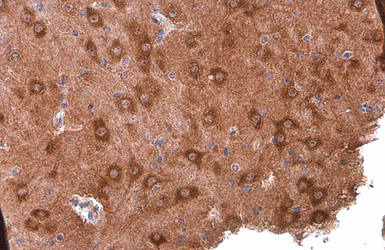

PYK2 antibody [GT858] detects PYK2 protein at cytoplasm by immunohistochemical analysis.

Sample: Paraffin-embedded rat thymus gland.

PYK2 stained by PYK2 antibody [GT858] (GTX634162) diluted at 1:200.

Antigen Retrieval: Citrate buffer, pH 6.0, 15 min